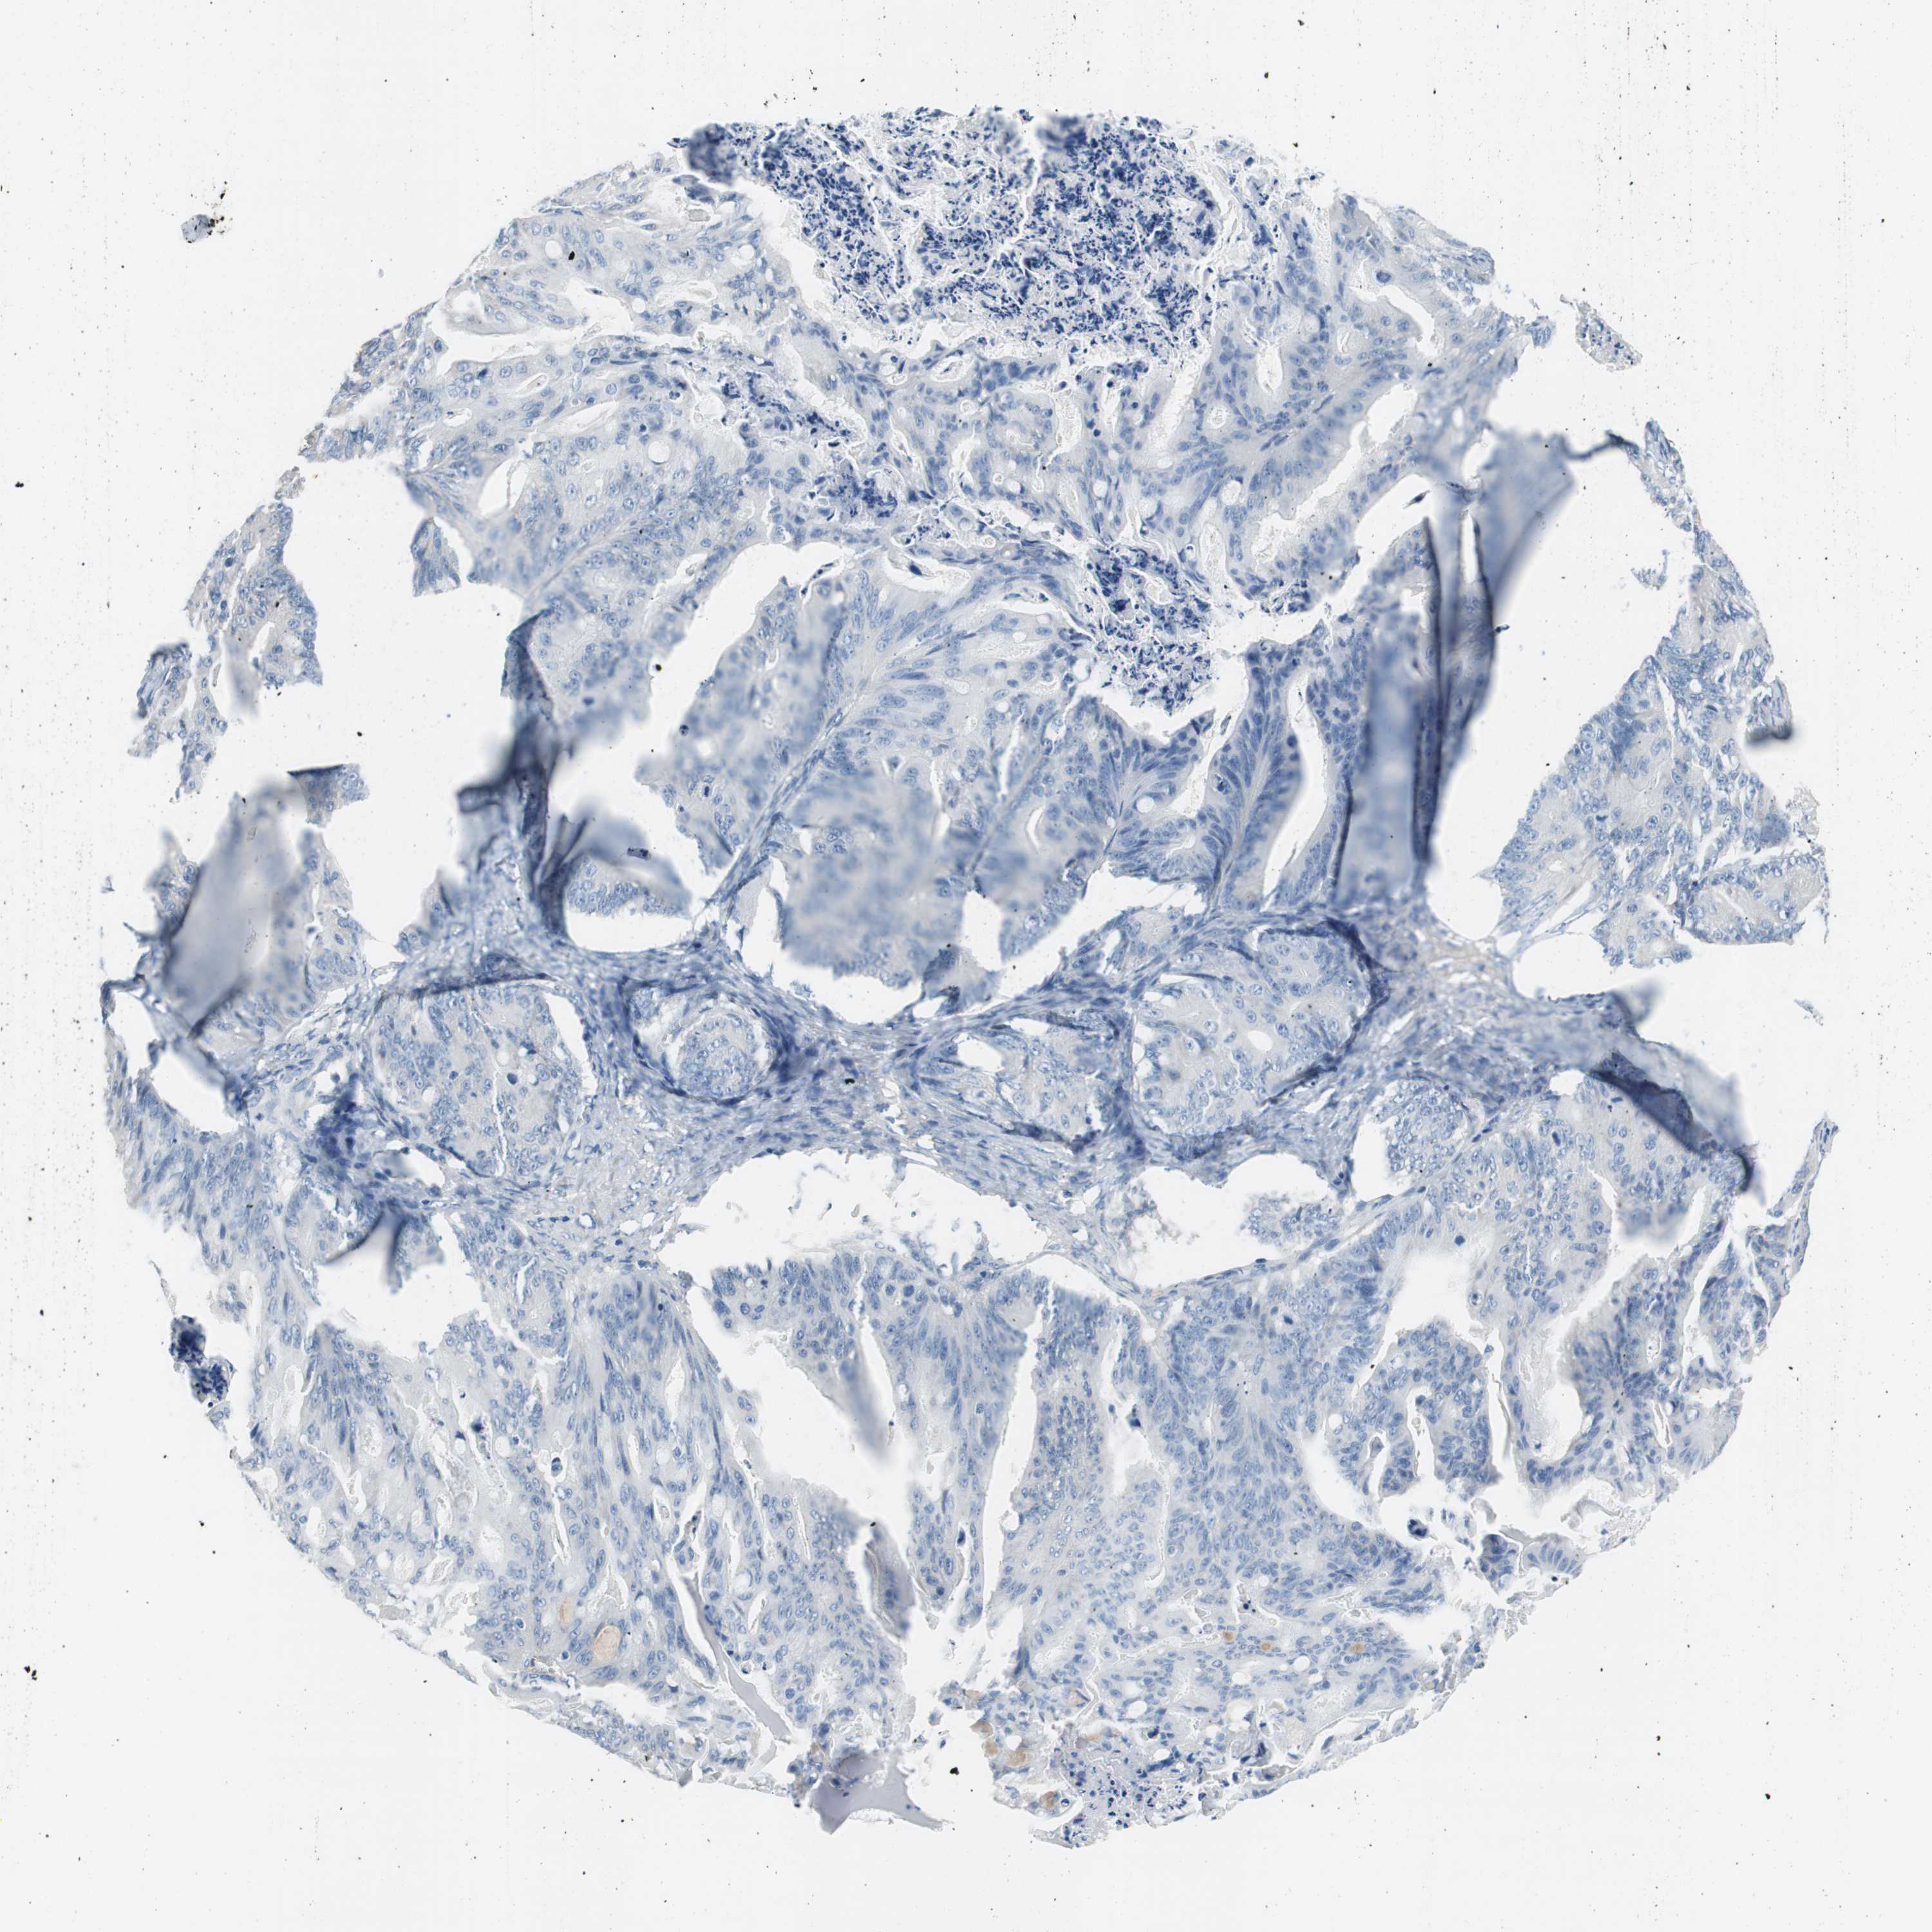

OVARIAN CANCER - Protein expressioni

A mouse-over function shows sample information and annotation data. Click on an image to view it in a full screen mode. Samples can be filtered based on level of antibody staining by selecting one or several of the following categories: high, medium, low and not detected. The assay and annotation is described here.

Note that samples used for immunohistochemistry by the Human Protein Atlas do not correspond to samples in the TCGA dataset.

Antibody stainingi

Antibody staining in the annotated cell types in the current human tissue is reported as not detected, low, medium, or high, based on conventional immunohistochemistry profiling in selected tissues. This score is based on the combination of the staining intensity and fraction of stained cells.

Each image is clickable and will lead to virtual microscopy that enables deeper exploration of all samples and also displays staining intensity scores, fraction scores and subcellular localization as well as patient and tissue information for each sample.

Antibody HPA008055

Staining

High

Medium

Low

Not detected

Intensity

Strong

Moderate

Weak

Negative

Quantity

>75%

75%-25%

<25%

None

Location

Nuclear

Cytoplasmic/membranous

Cytoplasmic/membranous,nuclear

Cystadenocarcinoma, serous, NOS

Carcinoma, endometroid

Carcinoma, NOS

Cystadenocarcinoma, mucinous, NOS